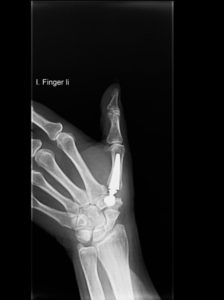

Eines dieser Verfahren ist der Einsatz einer Daumensattelgelenksprothese (Duokopfprothese). Sie hat anderen Eingriffen gegenüber wesentliche Vorteile, da Ihre Hand nach der Operation wieder schneller beweglich sein wird. Zudem verbessert sich Ihre Griffkraft und Sie werden schneller arbeitsfähig sein.

Rhizarthrose Behandlung mit einer Daumensattel-Gelenksprothese